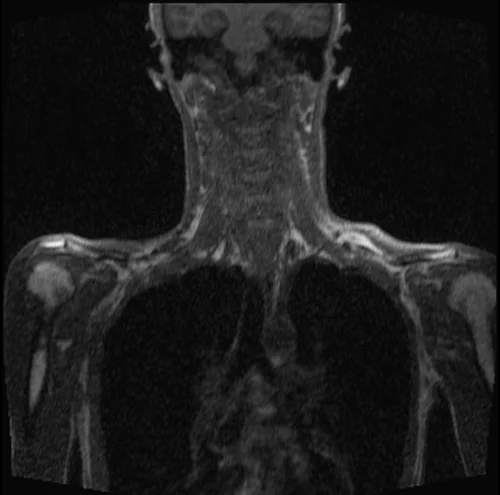

MRA subclavian artery coronal T1 3D FLASH images